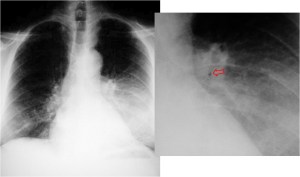

SIGNO DE LA PLEURA DESPEGADA o DIVISIÓN PLEURAL

Es un signo de empiema en la TC de tórax con contraste intravenoso. El signo consiste en el despegamiento de ambas hojas pleurales, que muestran un engrosamiento liso difuso y un realce con la administración de contraste. La imagen muestra la pleura visceral (flecha superior) y la pleura parietal (flecha inferior) despegadas. Ambas hojas se unen en los márgenes de la colección.

Otro ejemplo de este signo. El empiema muestra el despegamiento de las hojas pleurales visceral y parietal (flechas negras). Además, puede verse gas dentro del empiema (flecha blanca) y pulmón colapsado adyacente a la colección (flecha roja).